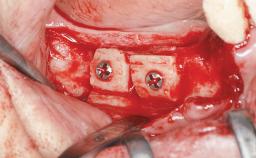

Guided Bone Regeneration (GBR) with a Particulated Autologous Graft and a ePTFE-Reinforced Membrane for Vertical Augmentation of a Single-Tooth Edentulous Space in the Esthetic Zone

A 47-year-old Caucasian woman with a single-tooth edentulous space at the site of the left maxillary canine was referred for treatment. She had undergone traumatic extraction of this impacted canine several months before referral. Her chief complaint was the dissatisfying appearance of her smile. The patient desired a stable and esthetic rehabilitation of the site. Her dental history showed no evidence of periodontal disease or bruxism. She had no systemic diseases, was not taking any medications, and did not smoke. The extraoral examination revealed a high lip line and an inadequate soft-tissue volume at the defective canine site. Large black triangles were visible between the canine and its adjacent teeth.

Bone Augmentation Staged|Vertical

Augmentation Materials Autogenous chips|Membrane

Bone Volume Deficient vertically or deficient vertically AND horizontally